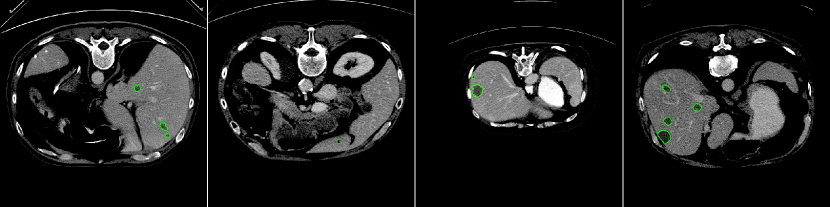

Experimental Results. Since we do not have the ground truth for the LiTS test set, we first perform the two-fold cross-validation on the training set to quantitatively and qualitatively evaluate the performance of our proposed method. We obtain Dice per case and some visual samples are presented in Fig. 6.

By evaluating on the test set of the LiTS challenge, we list in Table 1 our result with comparison to those of the currently published approaches. According to the Dice score per case, the most important metric for measuring an algorithm’s performance on the LiTS challenge, our approach is at the second rank, following after the H-Dense U-Net [12], which however needs pre-training. In addition, our small lesion segmentation could be an add-on component to their method for a further improvement in segmenting small tumors as mentioned in their future work. Our experiment shows that the dice per case can be improved from 0.61 to 0.681 with the consideration of the small lesion segmentation. Worth to mention that, among the methods without pre-training and post-processing, our method has the best performance in terms of the dice per case score. Figure 7 reports some visual results of our predictions on the LiTS test set.

Observations on LiTS Annotations. As shown in Fig. 6, the LiTS annotations have both over-segmentation and under-segmentation issues. For the large lesions in both cases shown in Fig. 6, our predictions better fit lesions compared to the ground truth; while for the small lesions, our predictions locate more lesions potentially missing in the ground truth. Similar observations have been reported in [4]. Due to the imperfect ground truth provided by the LiTS challenge, we argue that the metrics computed against the ground truth probably could not be the only way to compare the segmentation results. Visual results could be considered as well and ours indicate the efficiency of our method.